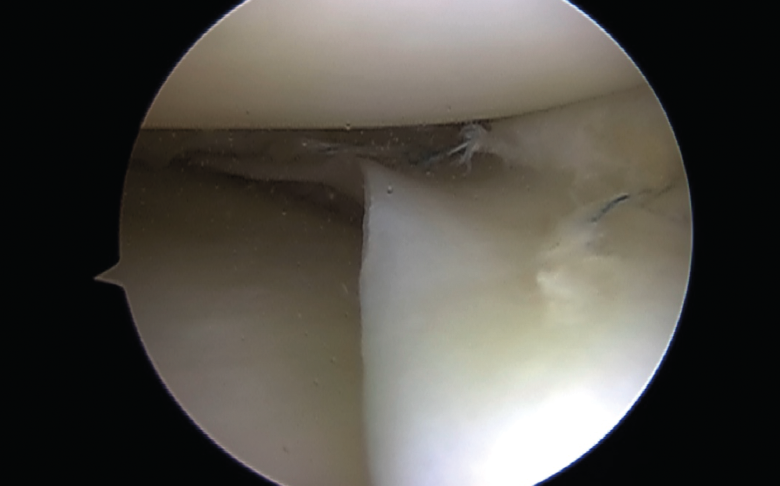

Biomecánicamente, se ha demostrado que una configuración de sutura vertical ya sea dentro-fuera o técnicas todo dentro cada 3 a 5 mm proporciona superioridad sobre la configuración horizontal(10)(Figura 4).

Tanto técnicas dentro-fuera como todo dentro se ha informado que tienen tasas de curación, complicaciones y resultados funcionales similares(11).

Figura 4. Asa de cubo: sutura con 3 puntos mediante técnica todo dentro.